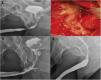

The bulbar urethra is the location where urethral stricture is most commonly observed. The most successful method for long and recurrent urethral stenosis is graft urethroplasty. The most successful graft source is buccal mucosa, with advantages like easy adaptation to the corporeal bed, thick epithelium, thin lamina propria with rich vascular structure and easy ability to obtain the graft. In this study we aimed to retrospectively assess the outcomes and predictive factors affecting surgical success of our buccal mucosal graft urethroplasty surgery performed for bulbar urethra stenosis with moderate length.

ConclusionFor bulbar urethral stricture longer than 2 cm and with recurrence, the dorsal buccal mucosa graft replacement is a very successful method with low complication rates.